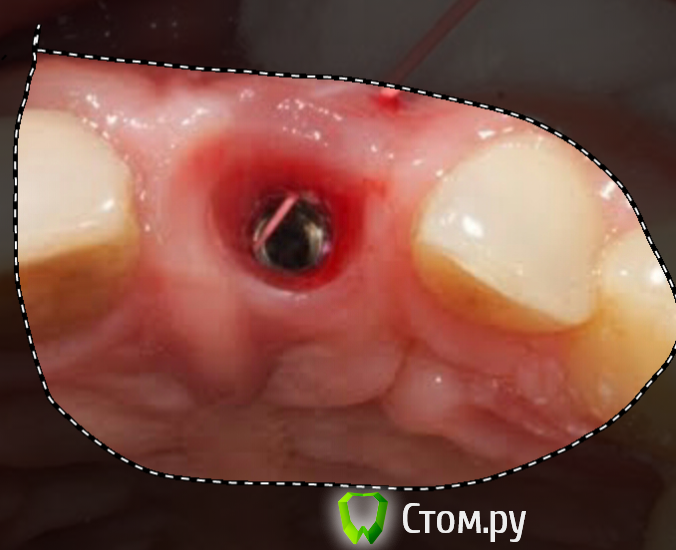

Bier Опубликовано 21 августа, 2014 Автор Поделиться Опубликовано 21 августа, 2014 Поехали дальше:Терапевт, выполняя мериленд, чуть было все не испортил, сделал временный зуб вплотную к десне, из-за отека лоскут "вдавился" во временный зуб и деформировался. На осмотре через 7 дней после операции я безжалостно спилил мешающую часть.http://img-fotki.yandex.ru/get/6808/40752090.7/0_e6541_c671fcc3_orig.jpg вот так все зажило за 2 месhttp://img-fotki.yandex.ru/get/6747/40752090.7/0_e6542_21a378df_orig.jpg Приступили ко второму этапу, новое раскрытие и установка ДЦ абатмента (стандартный 15* с высокой шейкой)http://img-fotki.yandex.ru/get/6840/40752090.7/0_e6543_5124a75e_orig.jpghttp://img-fotki.yandex.ru/get/6817/40752090.7/0_e6544_a3afbea9_orig.jpghttp://img-fotki.yandex.ru/get/6829/40752090.7/0_e6545_554b655f_orig.jpg Небольшой стейк с бугра в.ч.http://img-fotki.yandex.ru/get/6821/40752090.7/0_e6549_5c90d128_orig.jpgи ушиваниеhttp://img-fotki.yandex.ru/get/6836/40752090.7/0_e6548_c1f2b2f9_orig.jpghttp://img-fotki.yandex.ru/get/6800/40752090.7/0_e654a_c6e3b1ff_orig.jpg Заживление на временной коронкеhttp://img-fotki.yandex.ru/get/6738/40752090.7/0_e654b_48b8389c_orig.jpg финал, через 2 месяца.http://img-fotki.yandex.ru/get/6732/40752090.7/0_e654c_62473345_orig.jpg 17 Ссылка на комментарий